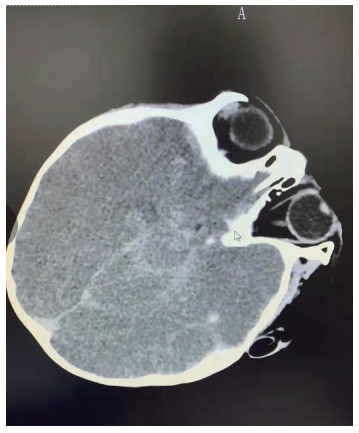

| 图 3 3月2日颅脑MRI |

图 1为颅内弥漫脑实质肿胀,脑沟脑回显示不清,脑室受压,部分脑沟内可见高密度影,右侧小脑幕密度增高。中线结构居中。副鼻窦内见软组织密度影。图 2为大脑皮层、小脑及脑干形态肿胀,呈稍长T2信号影,有类似束带征。图 3为后颅窝去骨辨减压+小脑部分切除术后复查: 脑疝征象明显好转。